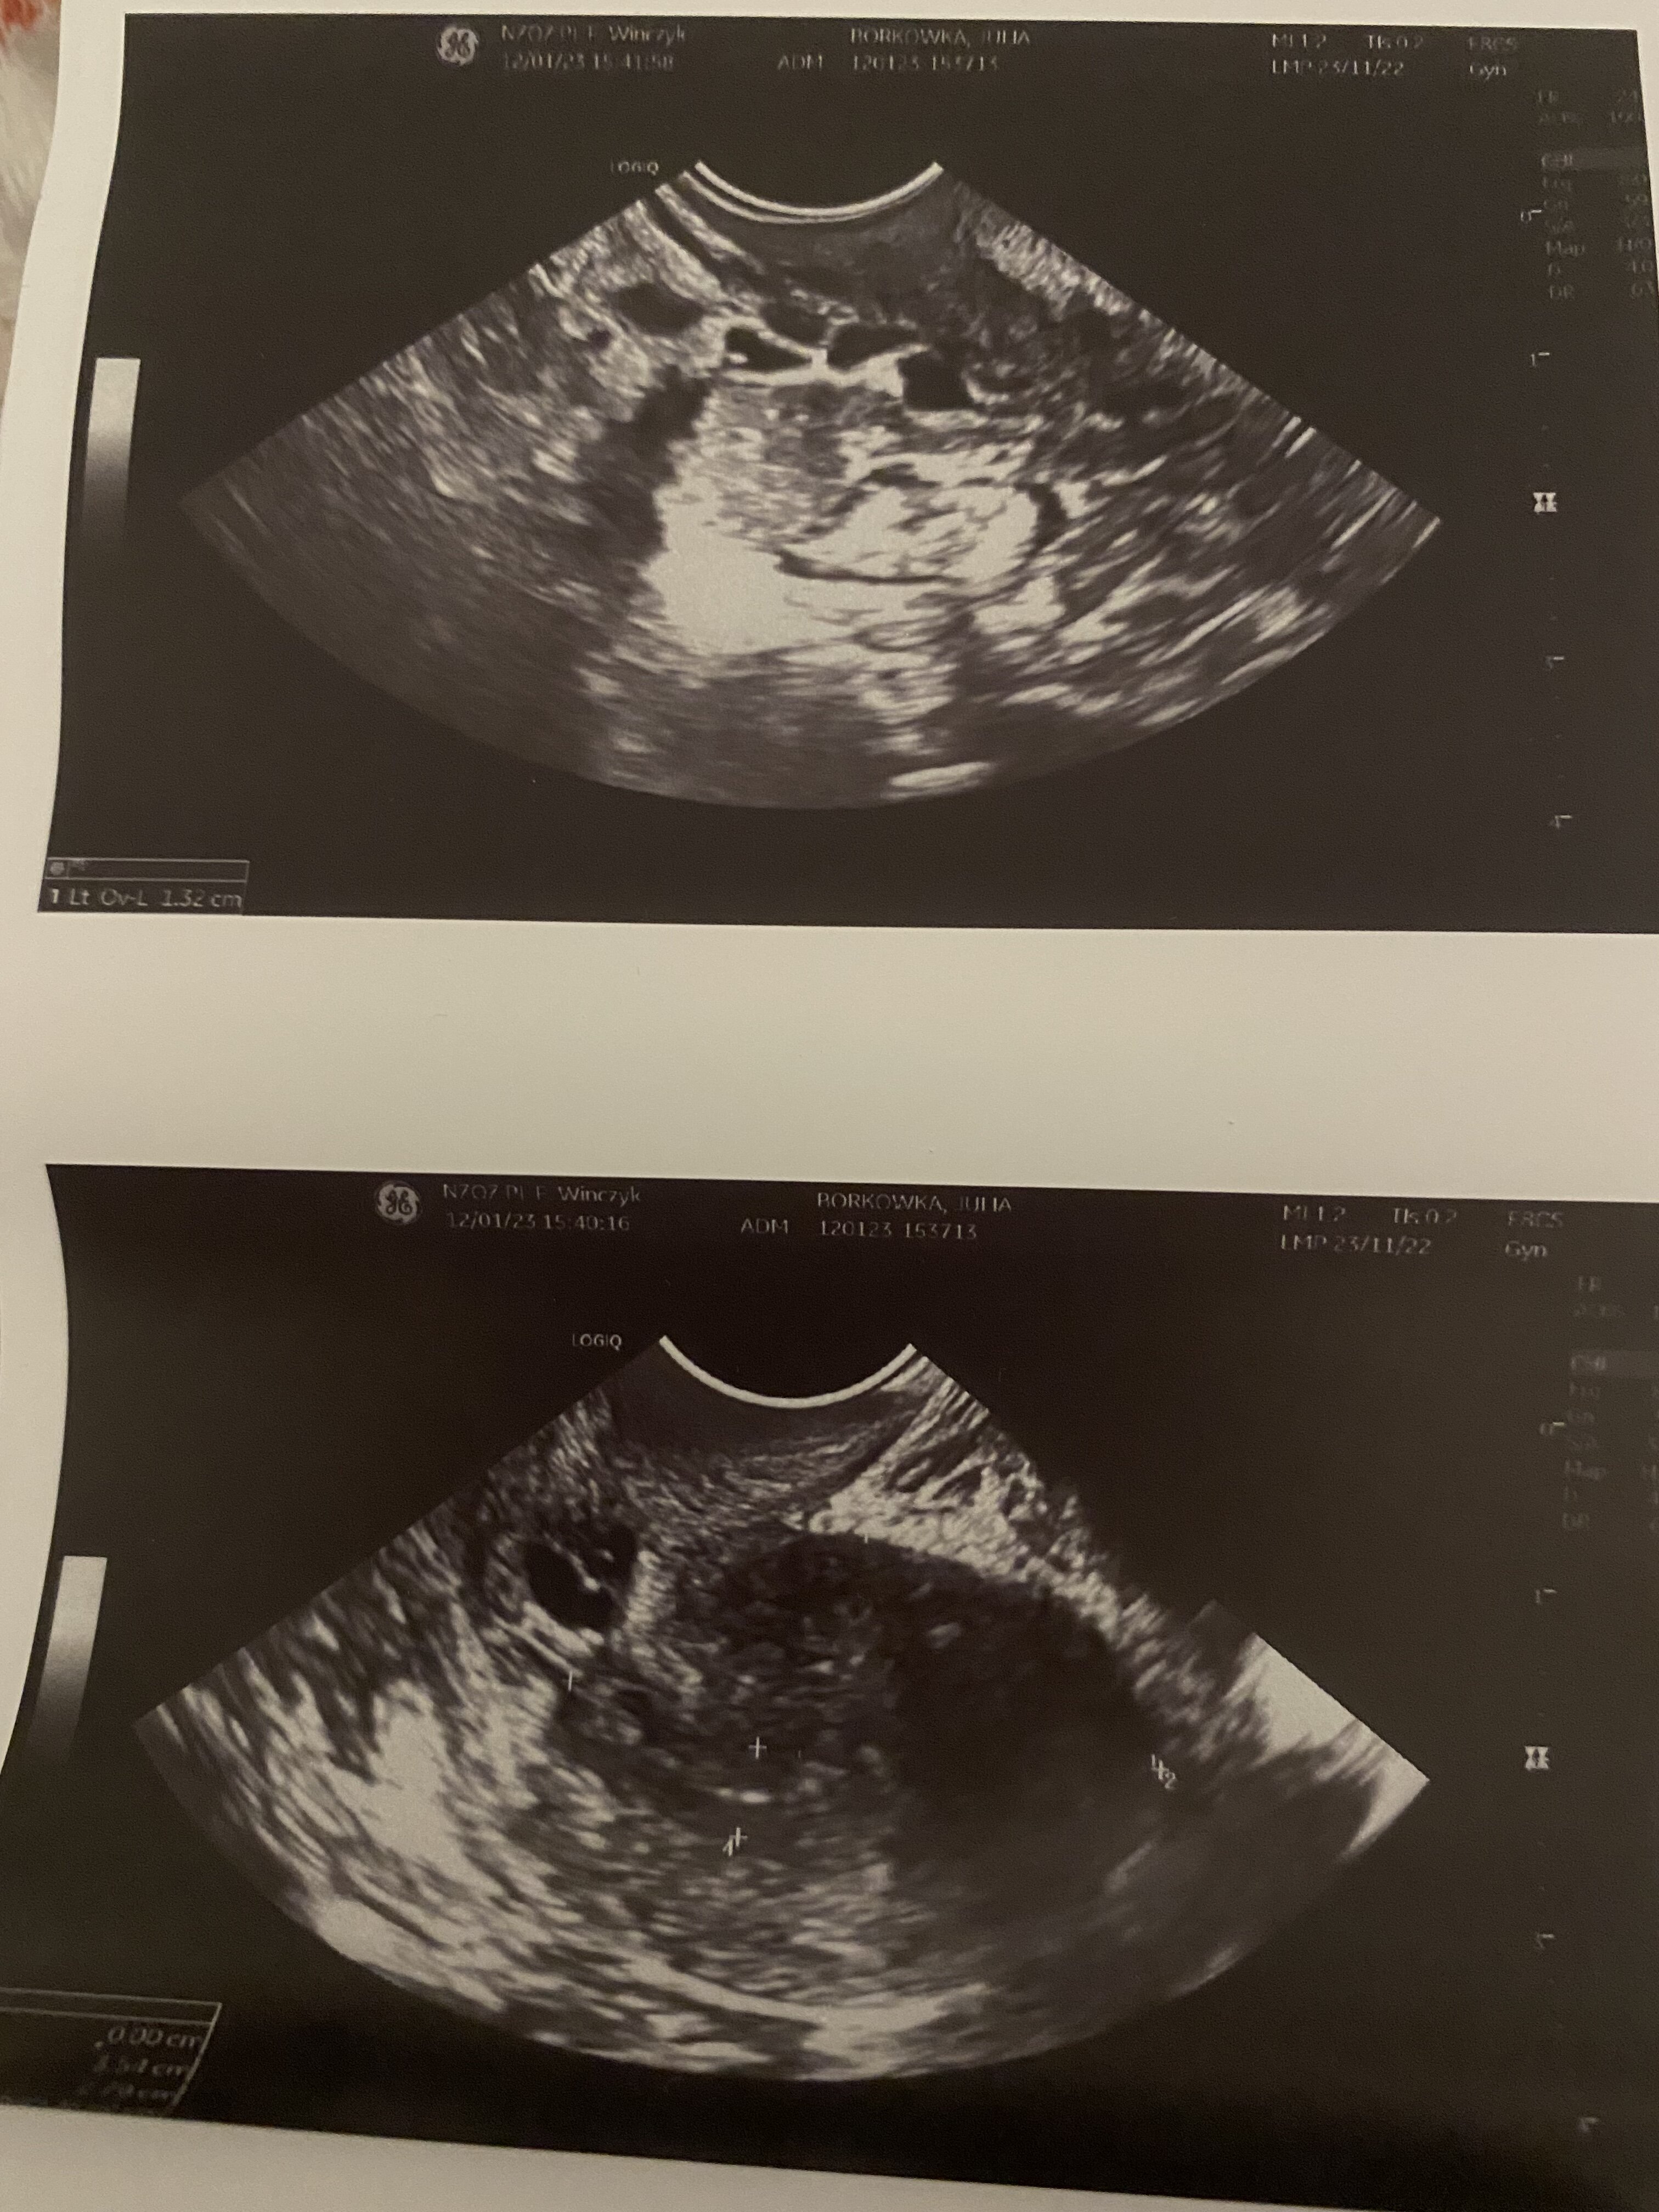

Hej czy to może być ciąża spóźnia mi się okres już 3 tygodnie robiłam test wyszedł negatywny byłam u ginekolog i pani stwierdziła że ciąża może mieć 7 tyg i 1 dzień mówiła że pęcherzyk się rozwija po złej stronie i może to być ciąża pozamaciczna albo poronienie wtórne też mówiła że to ciąża bliźniacza bo jakby dwa pęcherzyki były sama już nie wiem co mam myśleć przepisała mi duphaston na wywołanie miesiączki. Przesyłam zdjęcia usg.